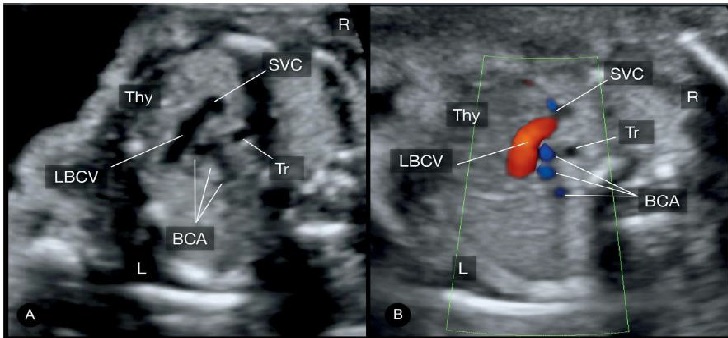

Hình 11: A & B mặt cắt ngang vị trí trung thất trên, cao hơn so với mặt cắt 3 mạch máu-khí quản. Hình ảnh tĩnh mạch cánh tay đầu trái (left brachiocephalic vein - LBCV). Chú ý vị trí giải phẫu của tĩnh mạch cánh tay đầu trái: Tuyến ức (Thy) ở phía trước và 3 động mạch tay đầu (three brachiocephalic arteries - BCA) ở phía sau. Tr: khí quản; L: trái; R: phải.